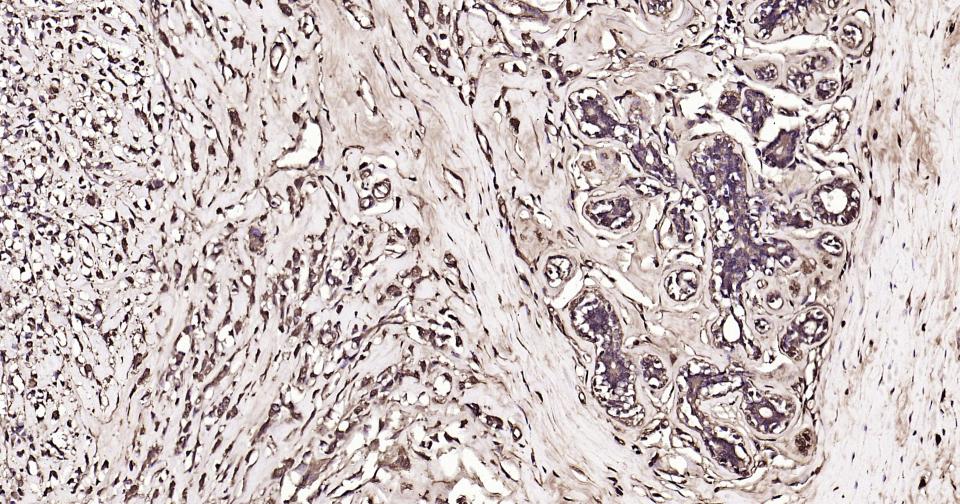

Paraformaldehyde-fixed, paraffin embedded Human Breast Cancer; Antigen retrieval by boiling in sodium citrate buffer (pH6.0) for 15 min; Antibody incubation with Calmodulin 1 Monoclonal Antibody, Unconjugated(bsm-61141R) at 1:200 overnight at 4°C, followed by conjugation to the SP Kit (Rabbit, SP-0023)and DAB (C-0010) staining.